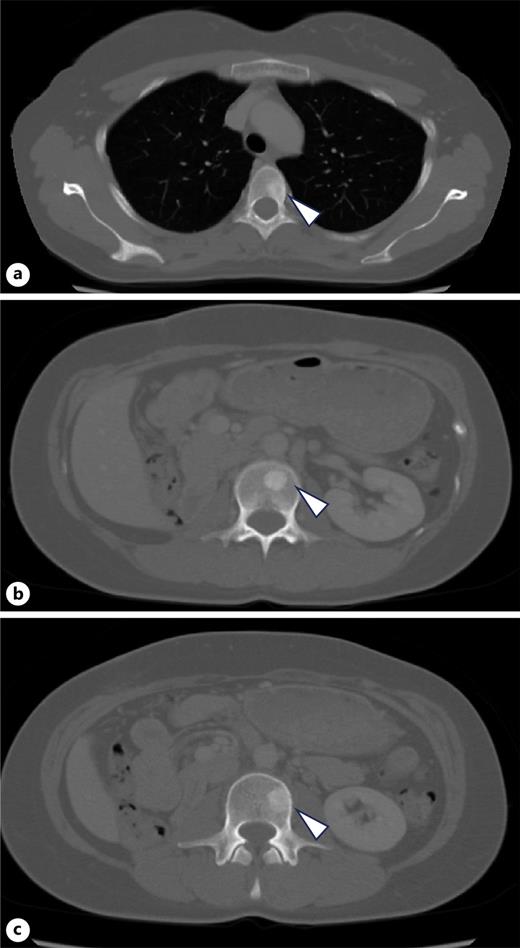

A 34-year-old woman presented with fever and right flank pain. Contrast-enhanced computed tomography (CT) revealed a 116 × 83 mm poorly enhanced solid mass replacing the right kidney, suspicious for RCC and tumor thrombus in the inferior vena cava below the hepatic vein inflow without apparent lymph node or distant metastases (shown in Fig. 1). Brain magnetic resonance imaging (MRI) showed no evidence of brain metastases, and bone scintigraphy revealed no abnormal uptake. The patient’s medical history included depression, and family history was notable for epilepsy in her brother and daughter. Therefore, the patient was diagnosed with non-clear cell RCC at the clinical stage cT3bN0M0. Concurrently, uterine leiomyomas were observed, along with a family history, raising suspicion for HLRCC. Open radical nephrectomy and inferior vena cava tumor thrombectomy were performed. Pathological findings revealed atypical tumor cells with irregular glandular structures and large nucleoli resembling nuclear inclusions. Immunohistochemical analysis showed loss of FH protein in the tumor cells, confirming the diagnosis of FH-deficient RCC, pT3bN0M0, stage III, WHO/ISUP grade 3 (shown in Fig. 2). PD-L1 expression and CD4/CD8-positive lymphocyte infiltration were observed, although most infiltrating lymphocytes were stromal with minimal intratumoral infiltration. Four weeks postoperatively, CT showed no recurrence. Adjuvant immunotherapy with pembrolizumab was initiated owing to the pT3b stage. Genetic counseling was performed with informed consent. Gene sequencing using a hybrid capture method identified a missense variant of FH c.698G>A (p.Arg233His) [NM_000143.4]. According to the ClinVar database (variation ID: 16236), the clinical significance of FH c.698G>A is pathogenic. Combined with her phenotype, we confirm the diagnosis of HLRCC. At week 9 of pembrolizumab therapy, CT revealed bone metastases at Th4, L2, and L3 (shown in Fig. 3). After discussing the available treatment options along with their respective benefits and drawbacks, the patient chose to pursue the most intensive therapy despite potential side effects. These oligometastases were treated with stereotactic body radiotherapy (SBRT) (24 Gy in two fractions). Therefore, systemic therapy with NIVO (240 mg) and cabozantinib (40 mg) was initiated. The patient remained stable disease for 16 months since the recurrence. Genomic testing using the FoundationOne CDx® panel identified the known FH mutation and genetic abnormalities in PIK3R1 and TP53; however, no additional actionable mutations were detected. Mutations in BRCA1/2 have been identified; however, these have been classified as variants of uncertain significance. After undergoing multidisciplinary genetic counseling, the patient consented to genetic testing of her 9-year-old daughter, which revealed the same FH gene mutation. Consequently, annual MRI screening of pediatric patients was initiated.